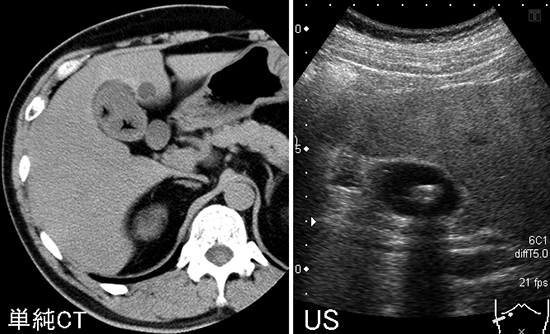

HOT ! 胆のうの中にあった石 胆石症、総胆管結石症|オリンパス おなかの健康ドットコム

胆のうの中にあった石 胆石症、総胆管結石症|オリンパス おなかの健康ドットコムの詳細情報

胆石症、総胆管結石症|オリンパス おなかの健康ドットコム。胆石(胆のう結石) | 宮城県大崎市 北みやぎ外科クリニック。胆道の病気】胆石とは? | 広島大学 第一外科。胆のうの中にあった石です人間の中にありました。標本用にどうですか?。胆石症、総胆管結石症|オリンパス おなかの健康ドットコム

• 胆石症、総胆管結石症|オリンパス おなかの健康ドットコム

• 胆石(胆のう結石) | 宮城県大崎市 北みやぎ外科クリニック

• 胆道の病気】胆石とは? | 広島大学 第一外科